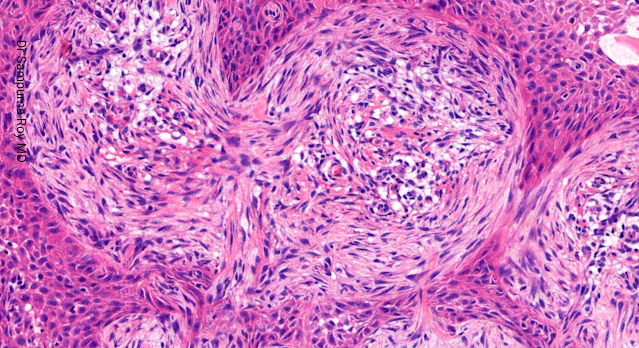

Dermatopathology Case 191 Get link Facebook X Pinterest Email Other Apps April 07, 2022 A 57-year-old man presented with a small papule on left side of the face. Answer Get link Facebook X Pinterest Email Other Apps Comments